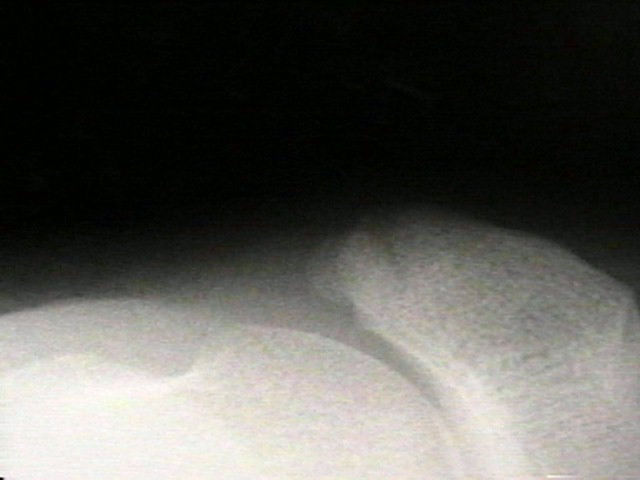

Radiographs

• radiographs may not be helpful if the accessory ossification is not ossified;

• the standard oblique of the foot (medial internal oblique view) will not show the accessory ossicle in profile;

• the lateral (external) oblique view is the radiograph of choice;

• although accessory navicular appears distinct from the navicular on x-rays, it is actually attached by fibrous tissue or cartilage;

Accessory Navicular 2 Accessory Navicular 3 Accessory Navicular 4